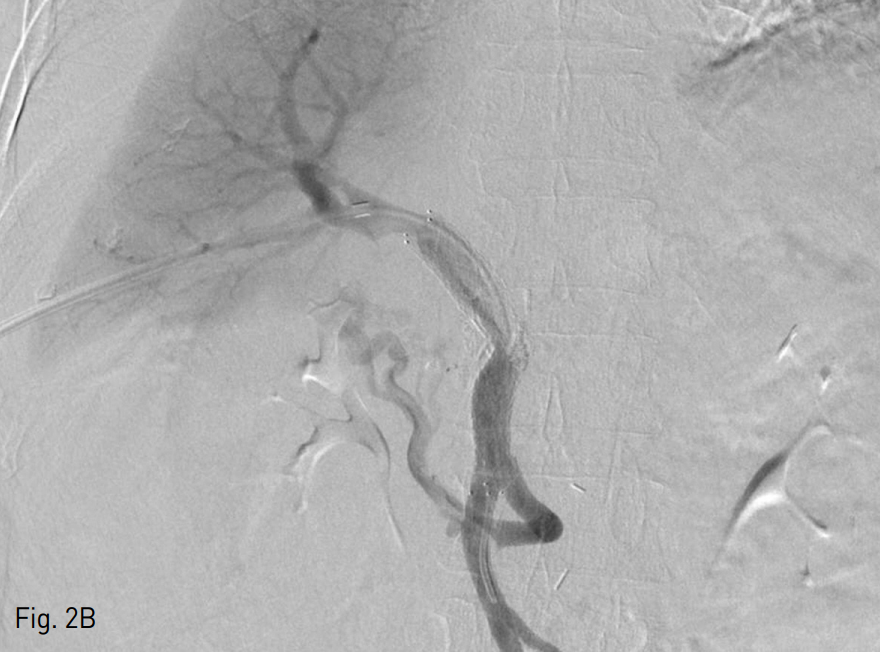

Fig. 2

A. Transhepatic portogram shows filling defect in portal vein (arrows), suggestive of thrombus and extravasation of contrast media (arrowheads) to jejunum.

B. Balloon dilatation, thrombectomy, and stent placement restored portal vein flow and decreased collateral flows.